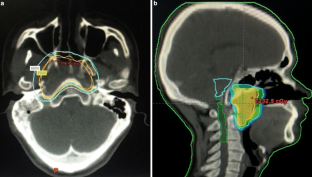

The endoscopic biopsy demonstrated that the mass was amyloid in nature. An extensive systemic workup revealed an absence of inflammatory process, systemic amyloidosis, or plasma cell dyscrasia. The patient was treated with a combination of surgery and radiotherapy, showing no evidence of recurrence or progression at his 1‑year follow-up.

Primary solitary amyloidosis is a rare form of amyloidosis. To the best of our knowledge, this is the first report of a nasopharyngeal amyloidosis case treated with excision and radiation leading to complete remission. Because of the difficulty for surgeons to achieve radical resection with such lesions, radiotherapy proved to be an excellent adjuvant treatment in this case.